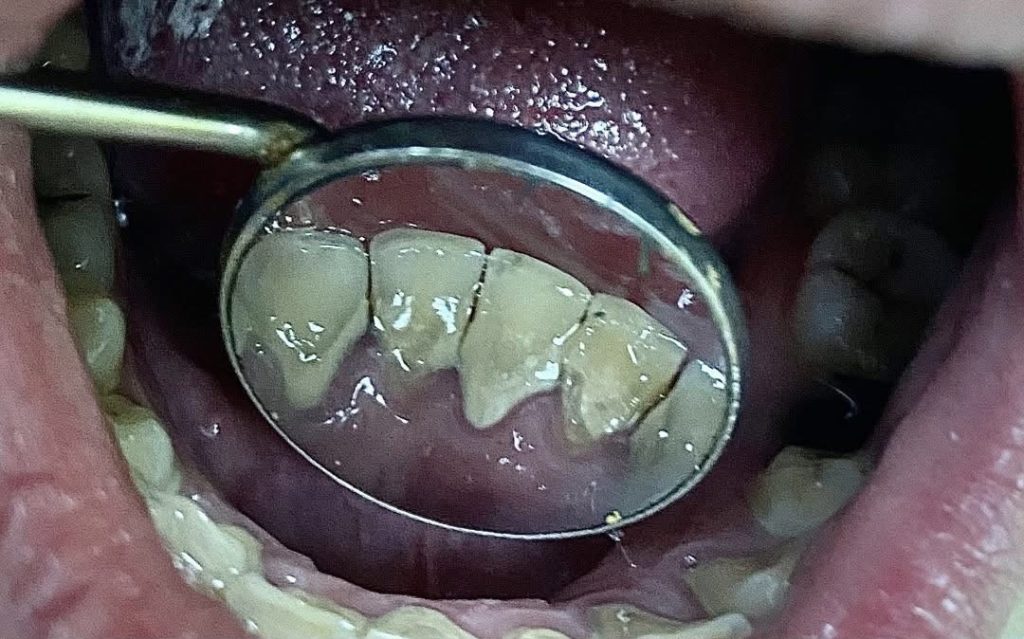

Slika: Prikaz zubnog kamenca praćenog sa upalom gingive na unutrašnjim plohama donjih frontalnih zuba

Profesionalno čišćenje zuba nije samo estetski tretman već važna stomatološka procedura. Za razliku od mekih naslaga koje se mogu ukloniti svakodnevnom oralnom higijenom, zubni kamenac se čvrsto veže za zubnu površinu i može se odstraniti isključivo profesionalnim stomatološkim tretmanom.

Njegovo prisustvo stvara hrapavu površinu pogodnu za daljnje nakupljanje bakterija, što dovodi do upale gingive, pojave krvarenja desni i razvoja gingivitisa. Ukoliko se ne ukloni na vrijeme, upalni proces može napredovati u parodontitis – hronično oboljenje koje uzrokuje razaranje potpornog aparata zuba i predstavlja jedan od vodećih uzroka gubitka zuba kod odraslih osoba.